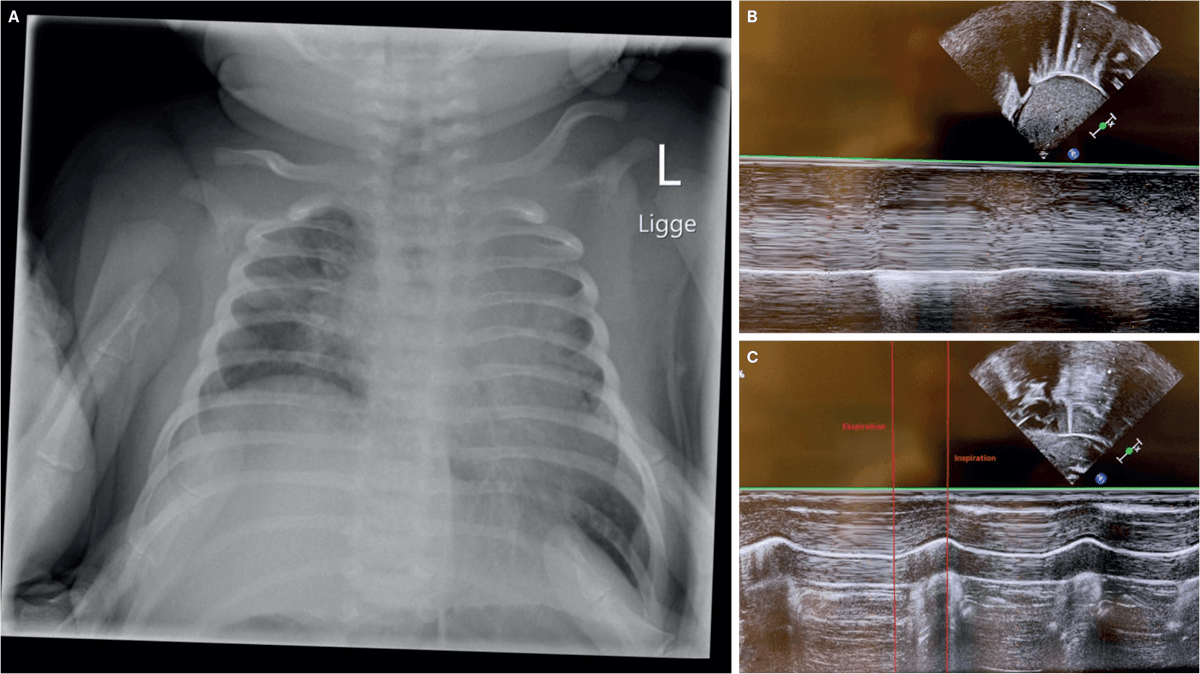

En 13 dage gammel pige blev henvist med besværet vejrtrækning. Moren var diagnosticeret med gestationel diabetes, og pigen var født ved manuel forløsning efter kortvarig skulderdystoci, med en fødselsvægt på 4,2 kg. Forældrene beskrev, at hun virkede øm i nakken. Hun fandtes med let besværet vejrtrækning og asymmetriske thorax-bevægelser, men var alment upåvirket og havde normal ilt-saturation. En blodprøve viste CO2-ophobning, og på røntgen af thorax sås ensidigt højtstående diafragmakuppel (A), hvilket rejste mistanke om paralyse af diafragma. En UL-skanning med M-mode bekræftede ensidigt stillestående diafragma (højre: B, normalt venstre: C).

Ved opfølgning efter fire mdr. var barnets vejrtrækning normaliseret, og en UL-skanning viste normale diafragmabevægelser.